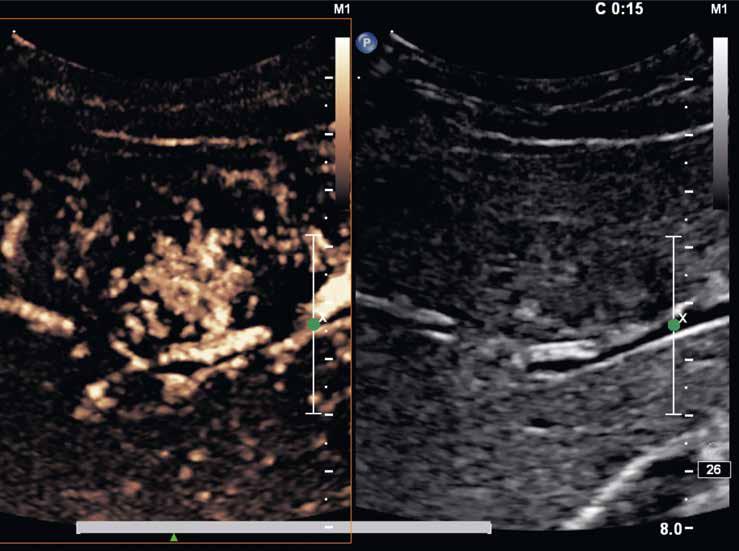

Na CEUS je v arteriální fázi patrný v levé polovině obrázku typický centrifugální charakter sycení ložiska, které je vidět v pravé polovině obrázku v B -módu (jako hypoechogenní) (6–8). Na CT (9) i MR (10) se ložisko (z obr. 4, 5) sytí homogenně, vyjma centrální vazivové jizvy, která zůstává hypodenzní.

V portovenózní fázi je ložisko izodenzní na CT (11), respektive izointenzní na MR (12).

V pozdní fázi je charakter ložiska stejný a nedochází k jeho vymývání ani na CT (13), ani na MR (14).

V centrální části ložiska je patrná vazivová jizva, která zůstává v arteriální fázi hypodenzní (9) a sytí se v pozdní fázi, kde je oproti zbytku ložiska hyperdenzní (13). Na MR je v T1-váženém obraze vazivová jizva hypointenzní (15), v T2-váženém obraze hyperintenzní (16).

Na MR ve fázi ekvilibria je v levém laloku patrné vcelku izointenzní ložisko s naznačeným hyperintenzním periferním prstenčitým lemem (17).

Po 20 minutách při použití hepatospecifické kontrastní látky je ložisko izointenzní až lehce hyperintenzní (18).